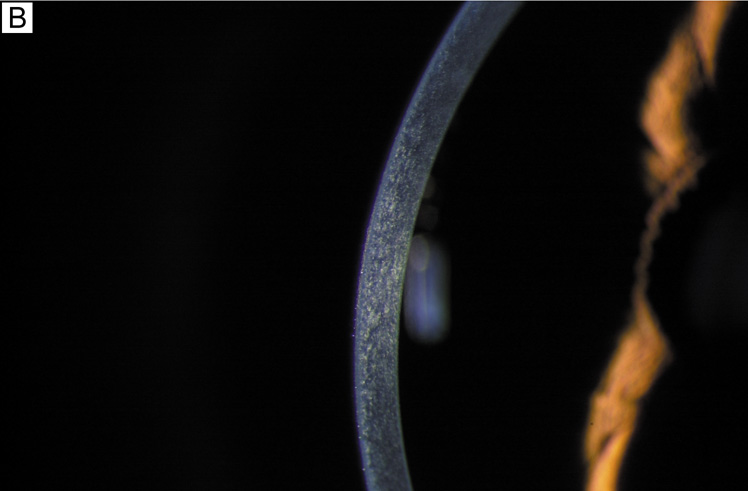

Having a sufficient number of endothelial cells to cover the posterior surface of the cornea along with having integrity of their cell junctions (tight and gap junctions), which are present in the intercellular spaces between endothelial cells, establishes the barrier function of endothelium (Figs. 12 and 22, 23, and 24). Clinically, the barrier function of the cornea can be assessed in vivo by the use of specular microscopy or confocal microscopy (endothelial cell density) or fluorophotometry (permability). In healthy human eyes, this barrier prevents the bulk flow of fluid from the aqueous humor to the corneal stroma, but does allow moderate diffusion of nutrients, water, and other metabolites to cross into the stroma through the 20 nm wide intercellular space. This leaky endothelial barrier may initially seem inefficient, but when one considers that most nutrients for all layers of the cornea come from the aqueous humor, the situation is reasonable.

Fig. 23. Scanning electron micrograph (1,000×) on the posterior surface of the corneal endothelium from a 65-year-old patient with healthy eyes. Note how the hexagonal endothelial cells form a uniform monolayer. Bar = 10 μm.